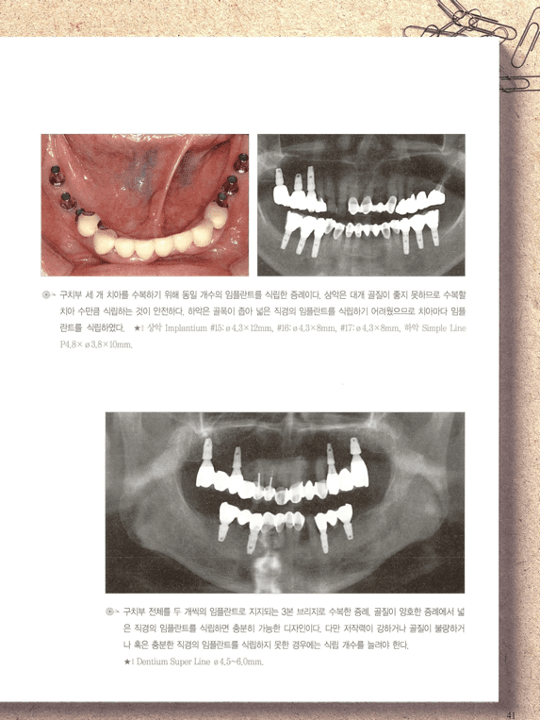

구치부 임플란트 식립 임상 증례 — 구강 내 사진과 파노라마 방사선 사진

[그림 3] 구치부 임플란트 식립 임상 증례. 잔존 치조골과 인접치 간 거리를 고려해 규격과 개수를 결정한 실제 식립 결과를 파노라마에서 확인합니다.